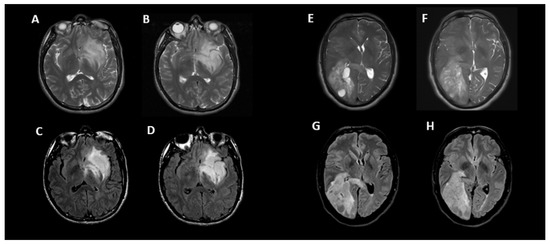

Figure 4 shows an example of two instances where the initial incorrect assignment of the 1p-19q status was correctly changed after using a predictive texture model such as CAT.

Figure 4. Two examples of correct changes made to T2-FLAIR mismatch evaluation with CAT. Axial T2 (A,B) and FLAIR (C,D) images in a 33-year-old male with IDH1 mutant glioma and non-co-deleted 1p/19q. During the initial interpretation, this was read as T2-FLAIR match but during the 2nd interpretation in conjunction with radiomic predicted result, this was correctly changed to T2-FLAIR mismatch. In this case, the heterogeneity of signal in different parts of tumor may have contributed to the initial error. Although there is relative matched signal between (A,C), there is subtle suppression of signal within the lower part of this tumor seen on (B,D) images. Axial T2 (E,F) and FLAIR (G,H) images in a 50-year-old male with IDH1 mutant glioma and co-deleted 1p/19q. During the initial interpretation this was read as T2-FLAIR mismatch; however, in 2nd interpretation in conjunction with radiomic predicted result, this was correctly changed to match. In this case, the prevalence of multiple small cystic components and their suppression on FLAIR images may have contributed to the initial error; however, when comparing (FH), it is apparent that the majority of signal is matched between T2 and FLAIR.